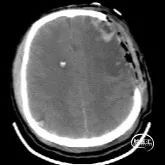

辅助检查:入院当天头部CT示:双侧额顶叶、左侧颞叶脑挫裂伤,最大截面约3.05×2.30cm,蛛网膜下腔出血。